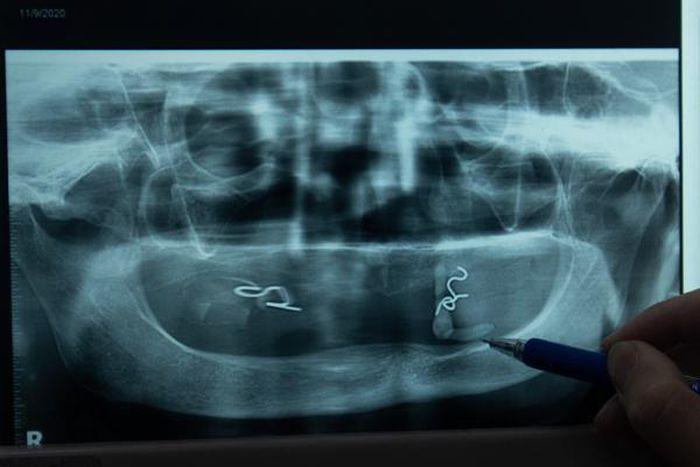

Đó là trường hợp của cụ bà Lê Thị Minh, 84 tuổi ở Mê Linh, Hà Nội. Bà cảm thấy vùng miệng sưng đau nhiều tháng nay nhưng đi khám nhiều lần vẫn không ra bệnh. Khi đến Bệnh viện Việt Nam - Cu Ba, Hà Nội thăm khám, bác sĩ mới phát hiện bên trong miệng cụ Minh có viên sỏi tuyến nước bọt kích thước 1,3x0,4 cm, tương tự hình chiếc răng.

Khi vào viện, một số trường hợp bác sĩ có thể sờ thấy viên sỏi nằm ngay dưới sàn miệng, một số khác phải siêu âm, kiểm tra hình ảnh để đánh giá.

Mỗi năm bệnh viện chỉ tiếp nhận 10-15 trường hợp. Độ lớn của viên sỏi có thể nhỏ như đầu tăm đến to vài cm. Sỏi có thể nằm trong ống tuyến nước bọt (kích cỡ khoảng 2 mm) hoặc nằm trong tuyến nước bọt.

Trường hợp sỏi trong ống tuyến có kích cỡ dưới 4 mm, bác sĩ có thể phẫu thuật nội soi để nong và gắp sỏi hoặc rạch lấy sỏi. Kích thước lớn hơn, bác sĩ sẽ phải dùng sóng siêu âm, tán nhỏ sỏi trước khi lấy ra ngoài.